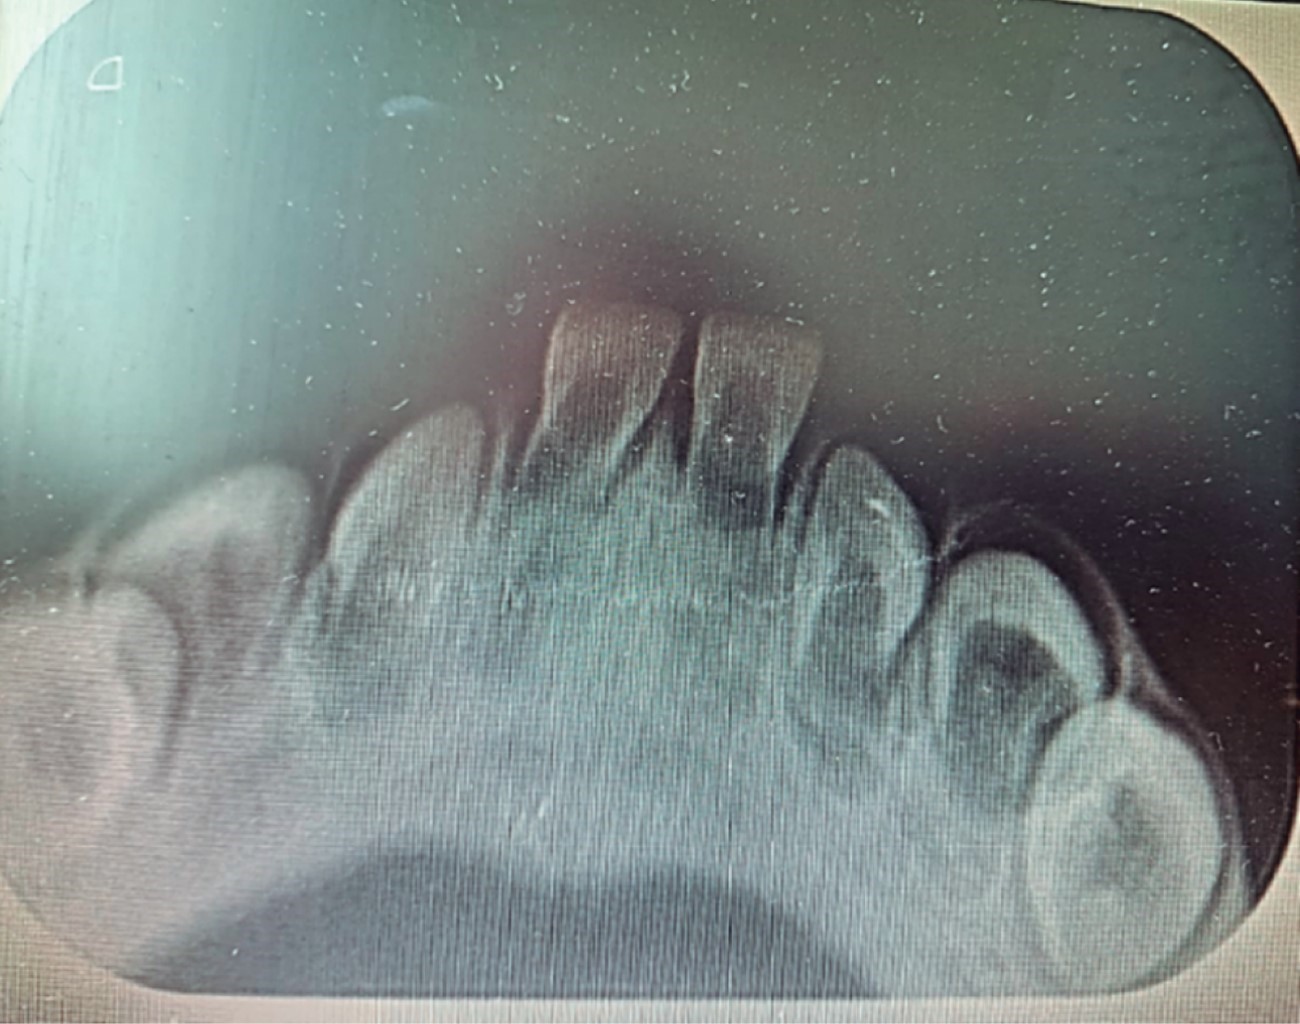

Como auxiliares de diagnóstico se pueden considerar la imagen radiográfica intraoral y la biopsia, la primera con la finalidad de valorar las condiciones de los órganos dentarios asociados a la lesión, determinar si pertenecen o no a la fórmula decidua, si se trata de supernumerarios y si su soporte sólo es mucoso u óseo también, estando así en posibilidad de complementar el diagnóstico inicial y seleccionar el tratamiento más conveniente; la segunda para conocer el contenido hístico de la lesión y confirmar el diagnóstico presuntivo en caso de que la evidencia clínica sea insuficiente o que la úlcera no ceda después del tratamiento elegido.4,9,11

Se toma radiografía oclusal inferior, donde se confirma que dichos órganos dentarios presentes en la cavidad bucal pertenecen a la fórmula dentaria primaria (Figura 2).

Se determina por sus características clínicas y hallazgos radiográficos el diagnóstico de: úlcera de Riga-Fede.